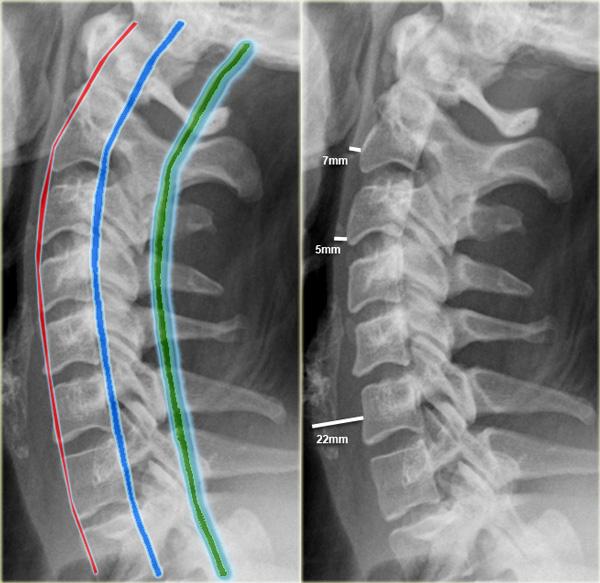

Tư thế thẳng bên (Lateral)

Tư thế thẳng bên là tư thế có giá trị chẩn đoán cao nhất.

Khoảng 85-90% các chấn thương cột sống có thể được phát hiện trên tư thế này.

Tiếp cận hệ thống:

-

Đánh giá sự thẳng hàng bằng cách theo dõi 3 đường viền:

- Đường viền phía trước nối các bờ trước của các thân đốt sống.

- Đường viền phía sau nối các bờ sau của các thân đốt sống.

- Đường viền gai-bản sống nối các nền của các mỏm gai.

- Trẻ nhỏ có thể có hình ảnh trượt đốt sống giả (pseudosubluxation) ở vùng cột sống cổ trên.

Khoang trước cột sống:

- Tại C2 không vượt quá 7 mm.

- Tại C3 và C4 không vượt quá 5 mm.

- Tại C6 khoang này rộng hơn do thực quản và cơ nhẫn hầu, nhưng không được vượt quá 22 mm ở người lớn hoặc 14 mm ở trẻ em dưới 15 tuổi.

- Ở trẻ em dưới 24 tháng tuổi, có thể có hiện tượng giãn rộng sinh lý của khoang trước cột sống trong thì thở ra gắng sức (ví dụ: khi khóc).

- Giãn rộng khoảng cách giữa các mỏm gai gợi ý tổn thương đứt dây chằng.